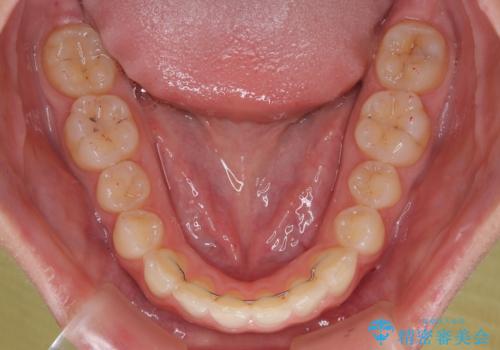

インビザライン単体でも同様の結果が得られる可能性がありますが、万が一奥歯がうまく後方移動できなかった場合、リカバリーが非常に大変となるため、事前に補助装置を併用して確実に結果が得られるように工夫をしています。